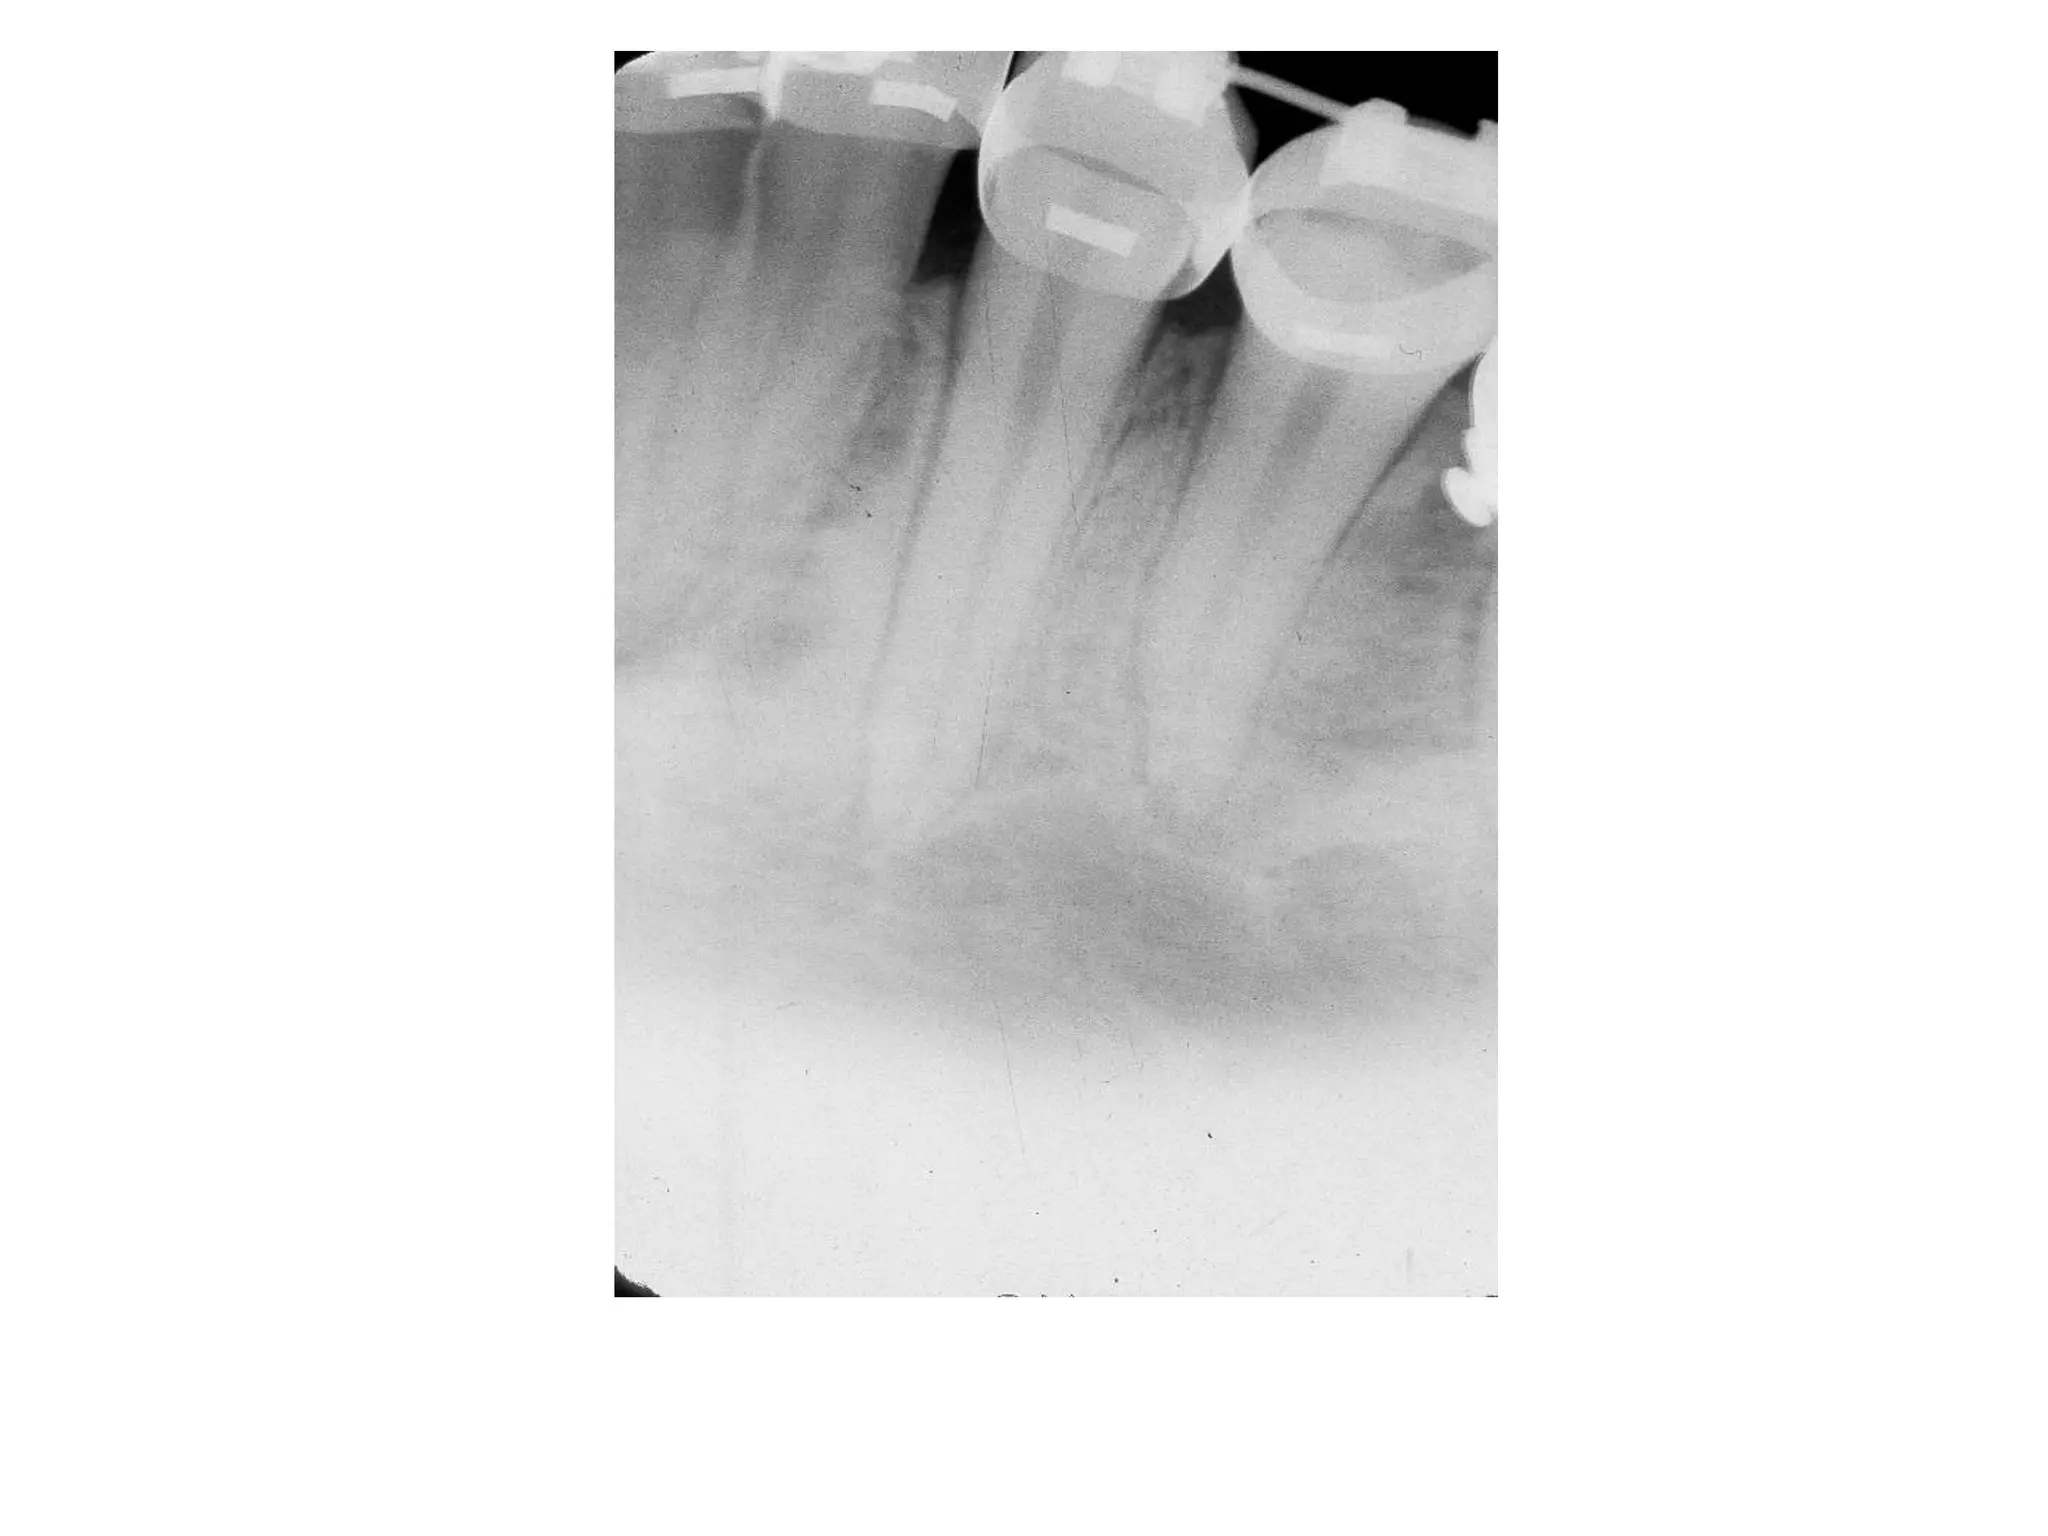

Severe Adult Periodontitis

Tooth mobility

Extensive horizontal bone

loss or vertical osseous

defects

Furcation involvement

Severe adult

periodontitis